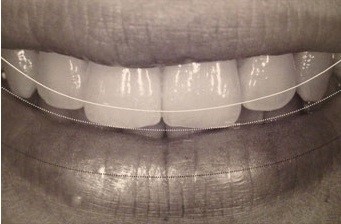

笑った時の下唇のアーチと歯並びのアーチを一致させます。こうすることで、口元の美しさが際立ちます。

著者: 山崎長郎 クインテッセンス出版: エステティック クラシフィケーションズ より引用